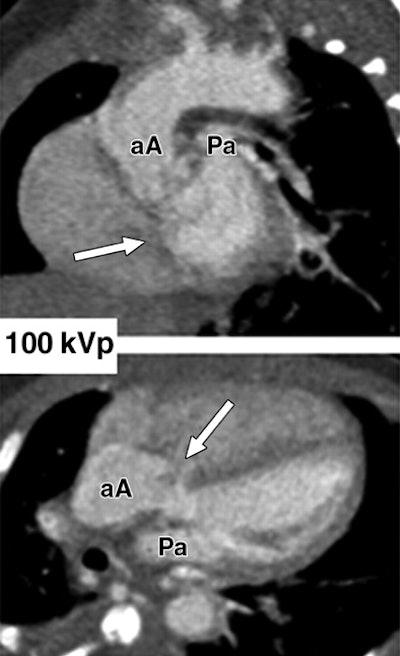

| Images show three different examples of congenital vascular abnormalities of chest evaluated with 64-slice CT with use of automatic tube current modulation. Oblique coronal maximum intensity projection images (upper row, above) and transverse section images (lower row, above) of patients scanned at 80 kVp and 100 kVp. Image set A (above) shows stenotic pulmonary artery (black arrowheads) in 6-month-old girl. Note difference in vessel caliber between right and left pulmonary arteries (white arrowhead). Image set B (below) shows left lower pulmonary vein (llPv) draining (black arrows) in right (rA) instead of left (lA) atrium in 2-year-old boy. ulPv = upper left pulmonary vein, rV = right ventricle, and lV = left ventricle. Image set C (100 mAs, bottom) shows tetralogy of Fallot with large septal defect (white arrows), overriding ascending aorta (aA), and stenotic pulmonary artery (Pa) in 6-month-old boy. |